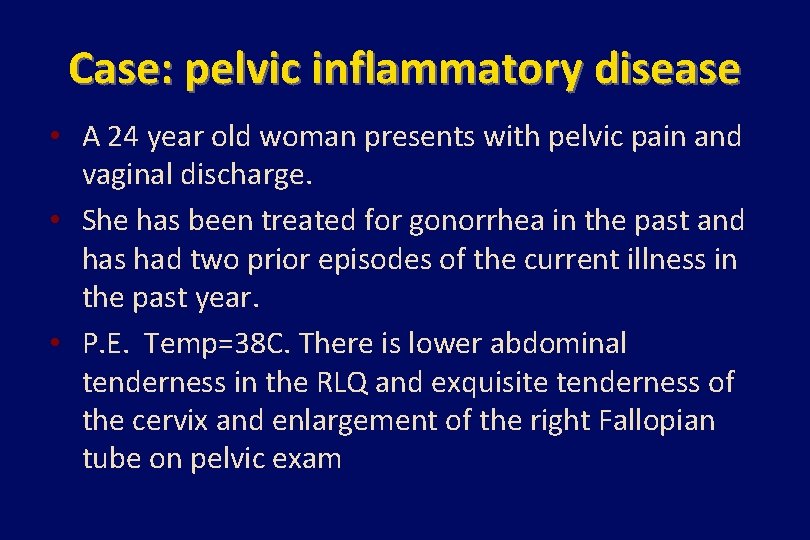

Case: pelvic inflammatory disease • A 24 year old woman presents with pelvic pain and vaginal discharge. • She has been treated for gonorrhea in the past and has had two prior episodes of the current illness in the past year. • P. E. Temp=38 C. There is lower abdominal tenderness in the RLQ and exquisite tenderness of the cervix and enlargement of the right Fallopian tube on pelvic exam